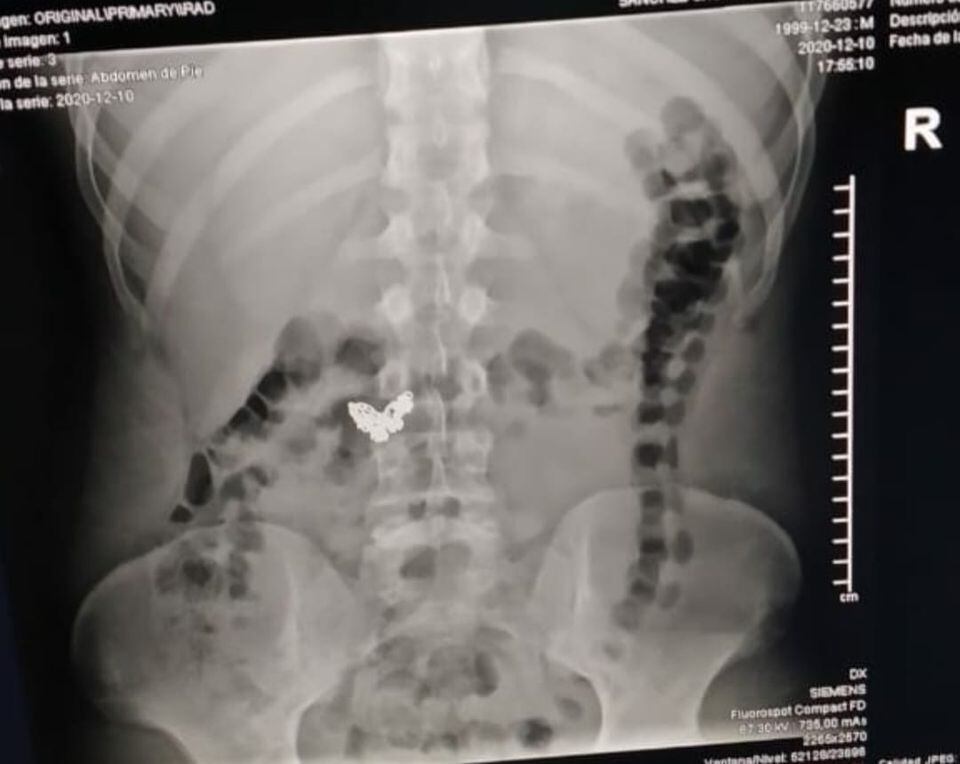

El uniformado habló con el fiscal sobre el posible paradero de la cadena, por lo que al tipo lo llevaron al Hospital Calderón Guardia y mediante unas placas le encontraron la cadena, luego lo pasaron a los Tribunales de Flagrancia de San José por el delito de robo simple.

El dueño de la cadena conversó vía telefónica con La Teja y se alegró al descubrir por medio de una placa médica que el maleante se la había tragado.